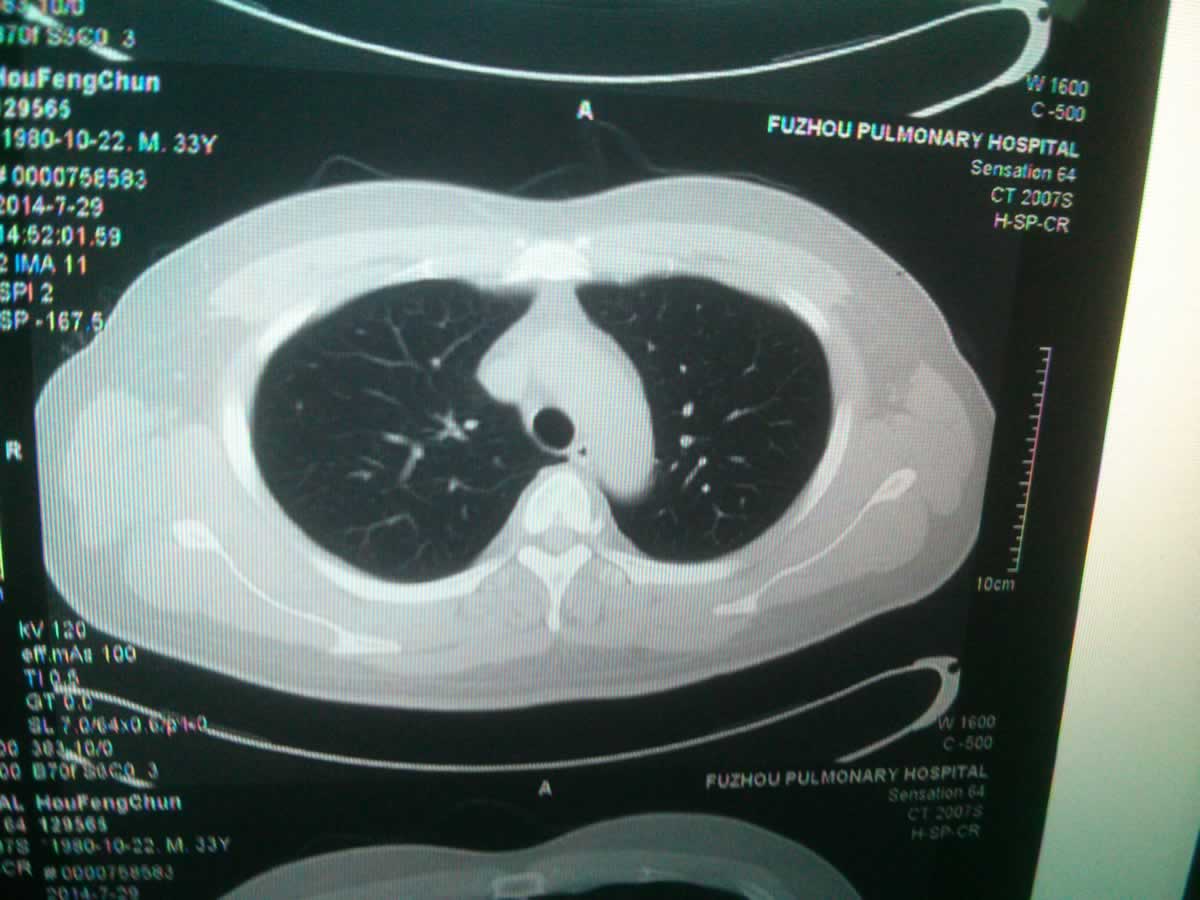

对于肺结节影的治疗,应首先明确肺结节影的性质,并根据结节的性质进行治疗,如下所示:

良性结节:炎症、出血、结核、纤维化等可导致肺部良性结节。如为炎症,有明显咳嗽、咳痰、气短等症状,听诊时有明显干湿罗音或痰鸣音,应加强痰培养和药敏试验,并给予敏感抗生素治疗、祛痰平喘等对症治疗。如果肺结节是由结核病引起的,患者有明显咳嗽、咳痰或痰中带血等症状,考虑到更可能是继发性肺结核,应尽快改善相关检查,定期进行抗结核治疗。

因此,对于良性肺结节,如果结节较小且无症状,可以定期复查,无需特殊治疗。如果出现症状,普通感染者将接受抗感染治疗,结核病患者将接受抗结核治疗。

恶性结节:如果诊断为恶性,建议尽快手术。如果患者没有手术指征且有其他部位转移,则应给予放疗或化疗,并根据多学科医生的咨询选择适当的治疗方案。